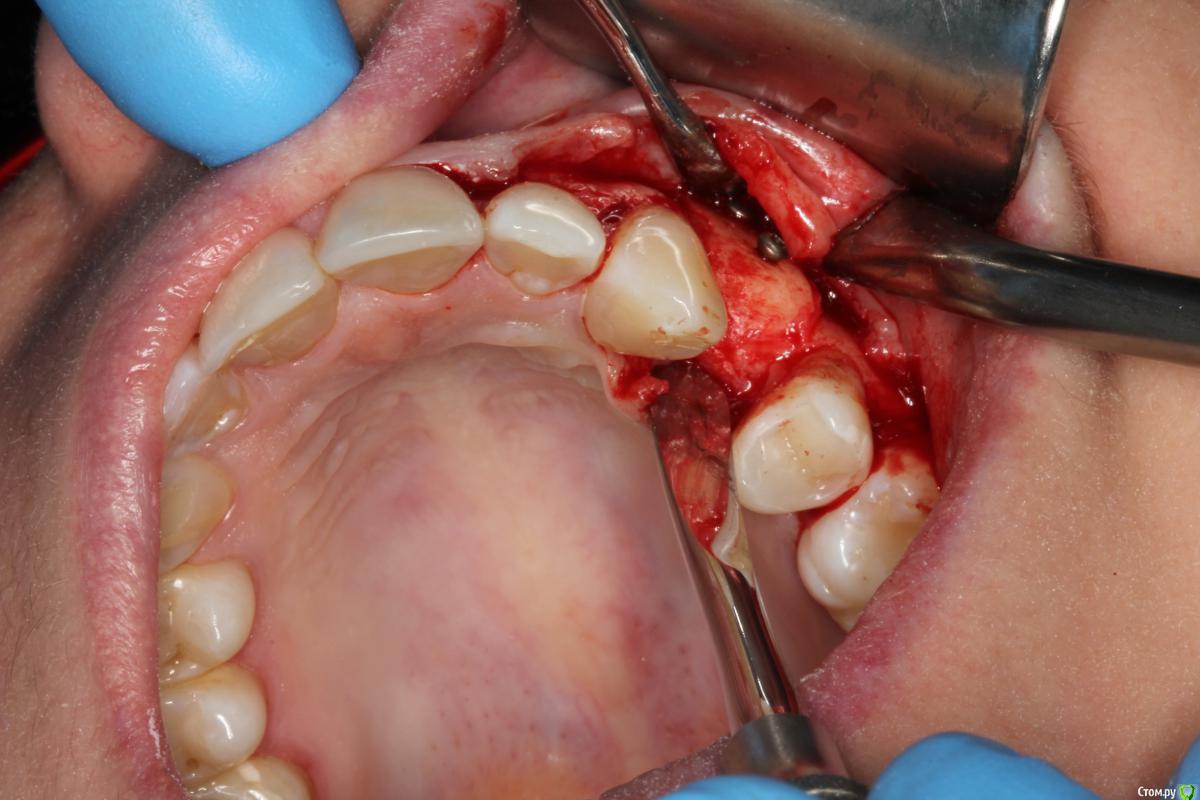

Den5 Опубликовано 24 декабря, 2014 Автор Поделиться Опубликовано 24 декабря, 2014 прикрутил аллоплант полгода назад.открылся.аллоплант норм-немного кровит.поставил Replace CC.Заглушил.Расщепил лоскут.Туда ССТ.На этапе ФДМ может еще подкину Ссылка на комментарий

Den5 Опубликовано 24 декабря, 2014 Автор Поделиться Опубликовано 24 декабря, 2014 фото снимков или рентген?Мембрана Evolution.Диастаз за штукатурен Putty Ссылка на комментарий

АнтонТЛТ Опубликовано 24 декабря, 2014 Поделиться Опубликовано 24 декабря, 2014 (изменено) Результат понравился Это блок с кортикалкой?Отслойка такая большая только для того чтоб винты выкрутить?Как пациенты относятся к алло? Изменено 24 декабря, 2014 пользователем АнтонТЛТ Ссылка на комментарий

Den5 Опубликовано 24 декабря, 2014 Автор Поделиться Опубликовано 24 декабря, 2014 Результат понравился Это блок с кортикалкой?Отслойка такая большая только для того чтоб винты выкрутить?Как пациенты относятся к алло?да,чтобы верхний винт выкрутить.блок с кортикалкой ,пациенту не говорил откуда блок,крепче спать будет 3 Ссылка на комментарий